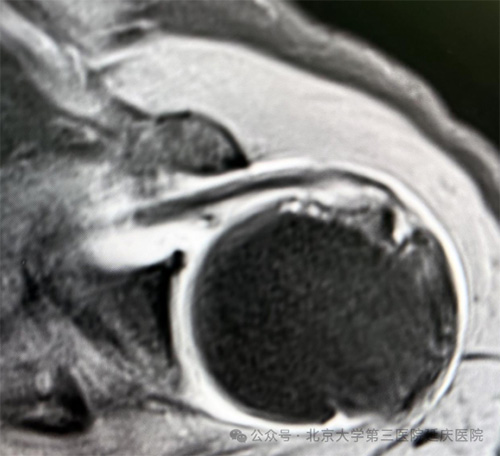

肩袖肌腱的MRI影像表现

2.超越静态的“动态评估”。很多情况下,静态影像(如MRI)就像一张地图,显示了体内“山川河流”布局,而您的肩痛,可能源于“车辆行驶”过程中的动态问题,这正是肌骨超声无可替代的优势。医生会通过超声探头显影观察肌腱、筋膜是否增粗增厚、周围是否存在积液、粘连,骨质是否破坏等。通过进行特定动作,以动态评估肌腱、周围神经是否被挤压、撞击,是否存在卡顿、撕裂或异常运动。有些小的损伤在静态时并不明显,但在特定角度或阻抗下,损伤处的异常分离或炎症渗出就会在超声下暴露无疑。

1.锁定疼痛元凶。引起肩痛的原因复杂多样,除了肩关节、肩袖疾患,颈椎病、肌筋膜炎、甚至心血管病都可能导致肩部疼痛。医生通过细致问诊,明确疼痛部位、性质、严重程度、持续时间、发作规律、诱发缓解因素等;通过特定试验、肌肉力量测试、活动度评估、压痛点位等体格检查进一步判断哪些关节、肌腱、神经、肌肉或滑囊出了问题;根据核磁共振等影像学检查,明确关节、软组织有无损伤、病变,与症状、体征相互印证,形成全面、立体的诊断依据。